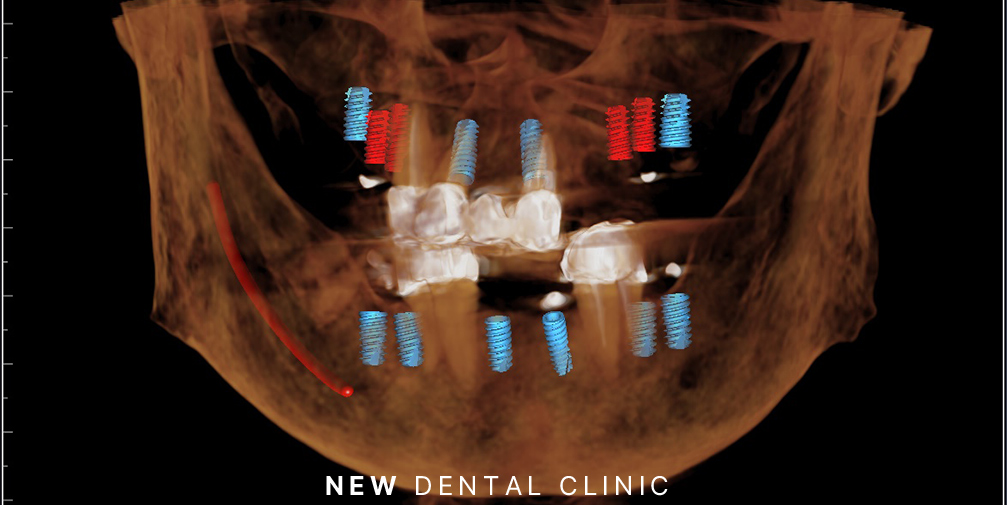

네비게이션 임플란트는 이러한 고민을 해결할 수 있는 방법으로 기존 수술법에서 더 발전된 기술로 CT를 활용하여 구강 내 해부학적 구조를 정밀하게 파악한 후, 그에 맞춰 식립하는 방법입니다. 3D CT를 통해 치아 상실 부위, 주변 치아, 신경, 치조골 상태 등을 정확하게 분석하고 이를 바탕으로 가이드를 제작하여 식립 과정에 따른 정확도를 높여 마치 자동차 네비게이션처럼 정확한 위치에 식립이 가능한 것입니다.

환자분께서는 겁도 많으셔서 수술에 대한 두려움이 있으셨는데요. 따라서 가이드를 이용한 네비게이션 임플란트로 계획을 수립하였습니다.

3D CT 촬영을 총해 가이드를 제작하여 장착한 모습인데요. 여러 개의 임플란트를 동시에 식립해야 하는 경우에도 계획을 통해 한 번에 진행할 수 있어 전체적인 치료 기간을 단축할 수 있다는 장점도 가지고 있습니다.